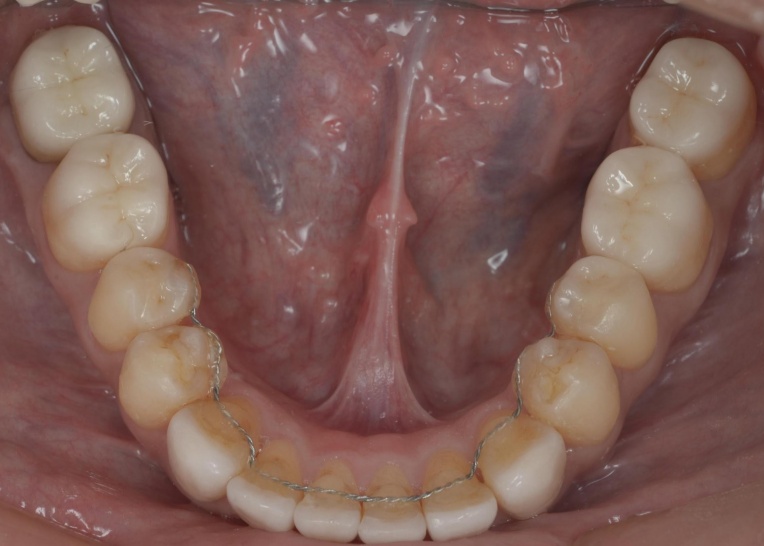

治療前

治療中

治療後